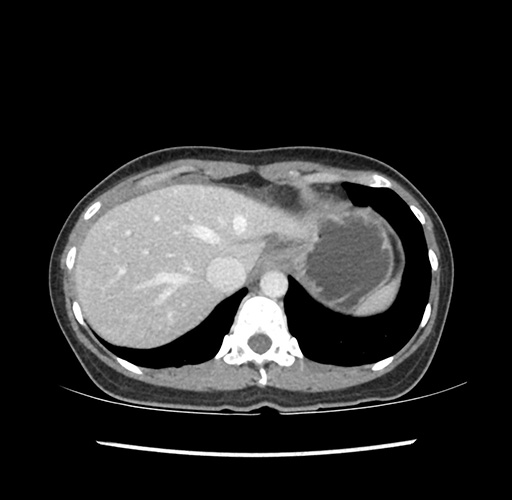

Imaging Analysis

Look through the patient's CT scan to identify any areas of concern for the necessary procedure.

Based on your CT findings, which issue(s) would give reason for "planned slowing down moment(s)" in this case?